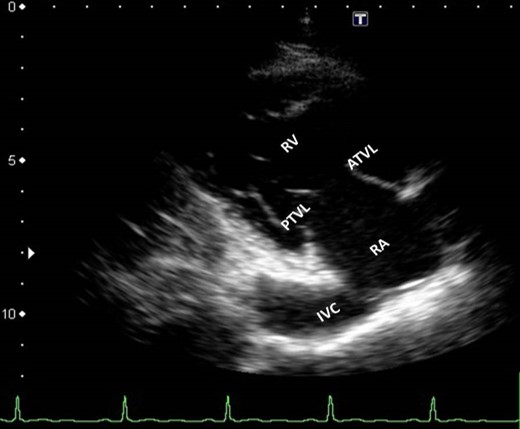

Subcostal IVC View